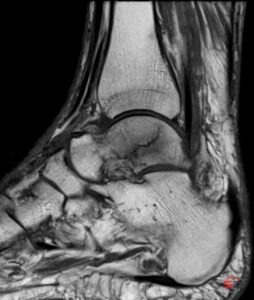

2. MRI – Goldstandard

Das MRI besitzt die höchste Sensitivität zur Detektion okkulter Frakturen. Charakteristische Befunde sind:

- Ausgeprägtes Knochenmarködem als Hauptmarker („bone bruise“)

- Darstellung subchondraler Impressionslinien und kleiner Frakturspalten

- Beurteilung von chondralen Begleitläsionen und Weichteilverletzungen

Insbesondere bei persistierenden Schmerzen trotz unauffälligem Röntgen und bei hoher klinischer Verdachtslage ist das MRI das Verfahren der Wahl.